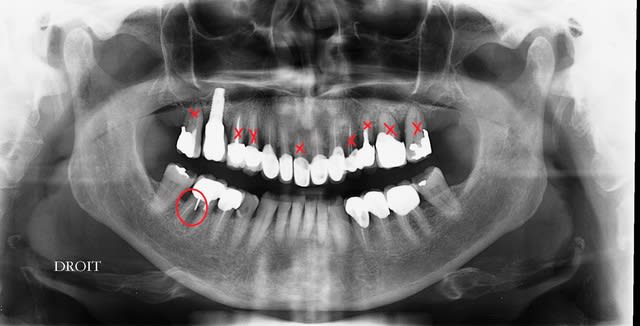

petit panoramique de contrôle, ce n'est pas gagné, mais ça semble aller dans le bon sens.

32?